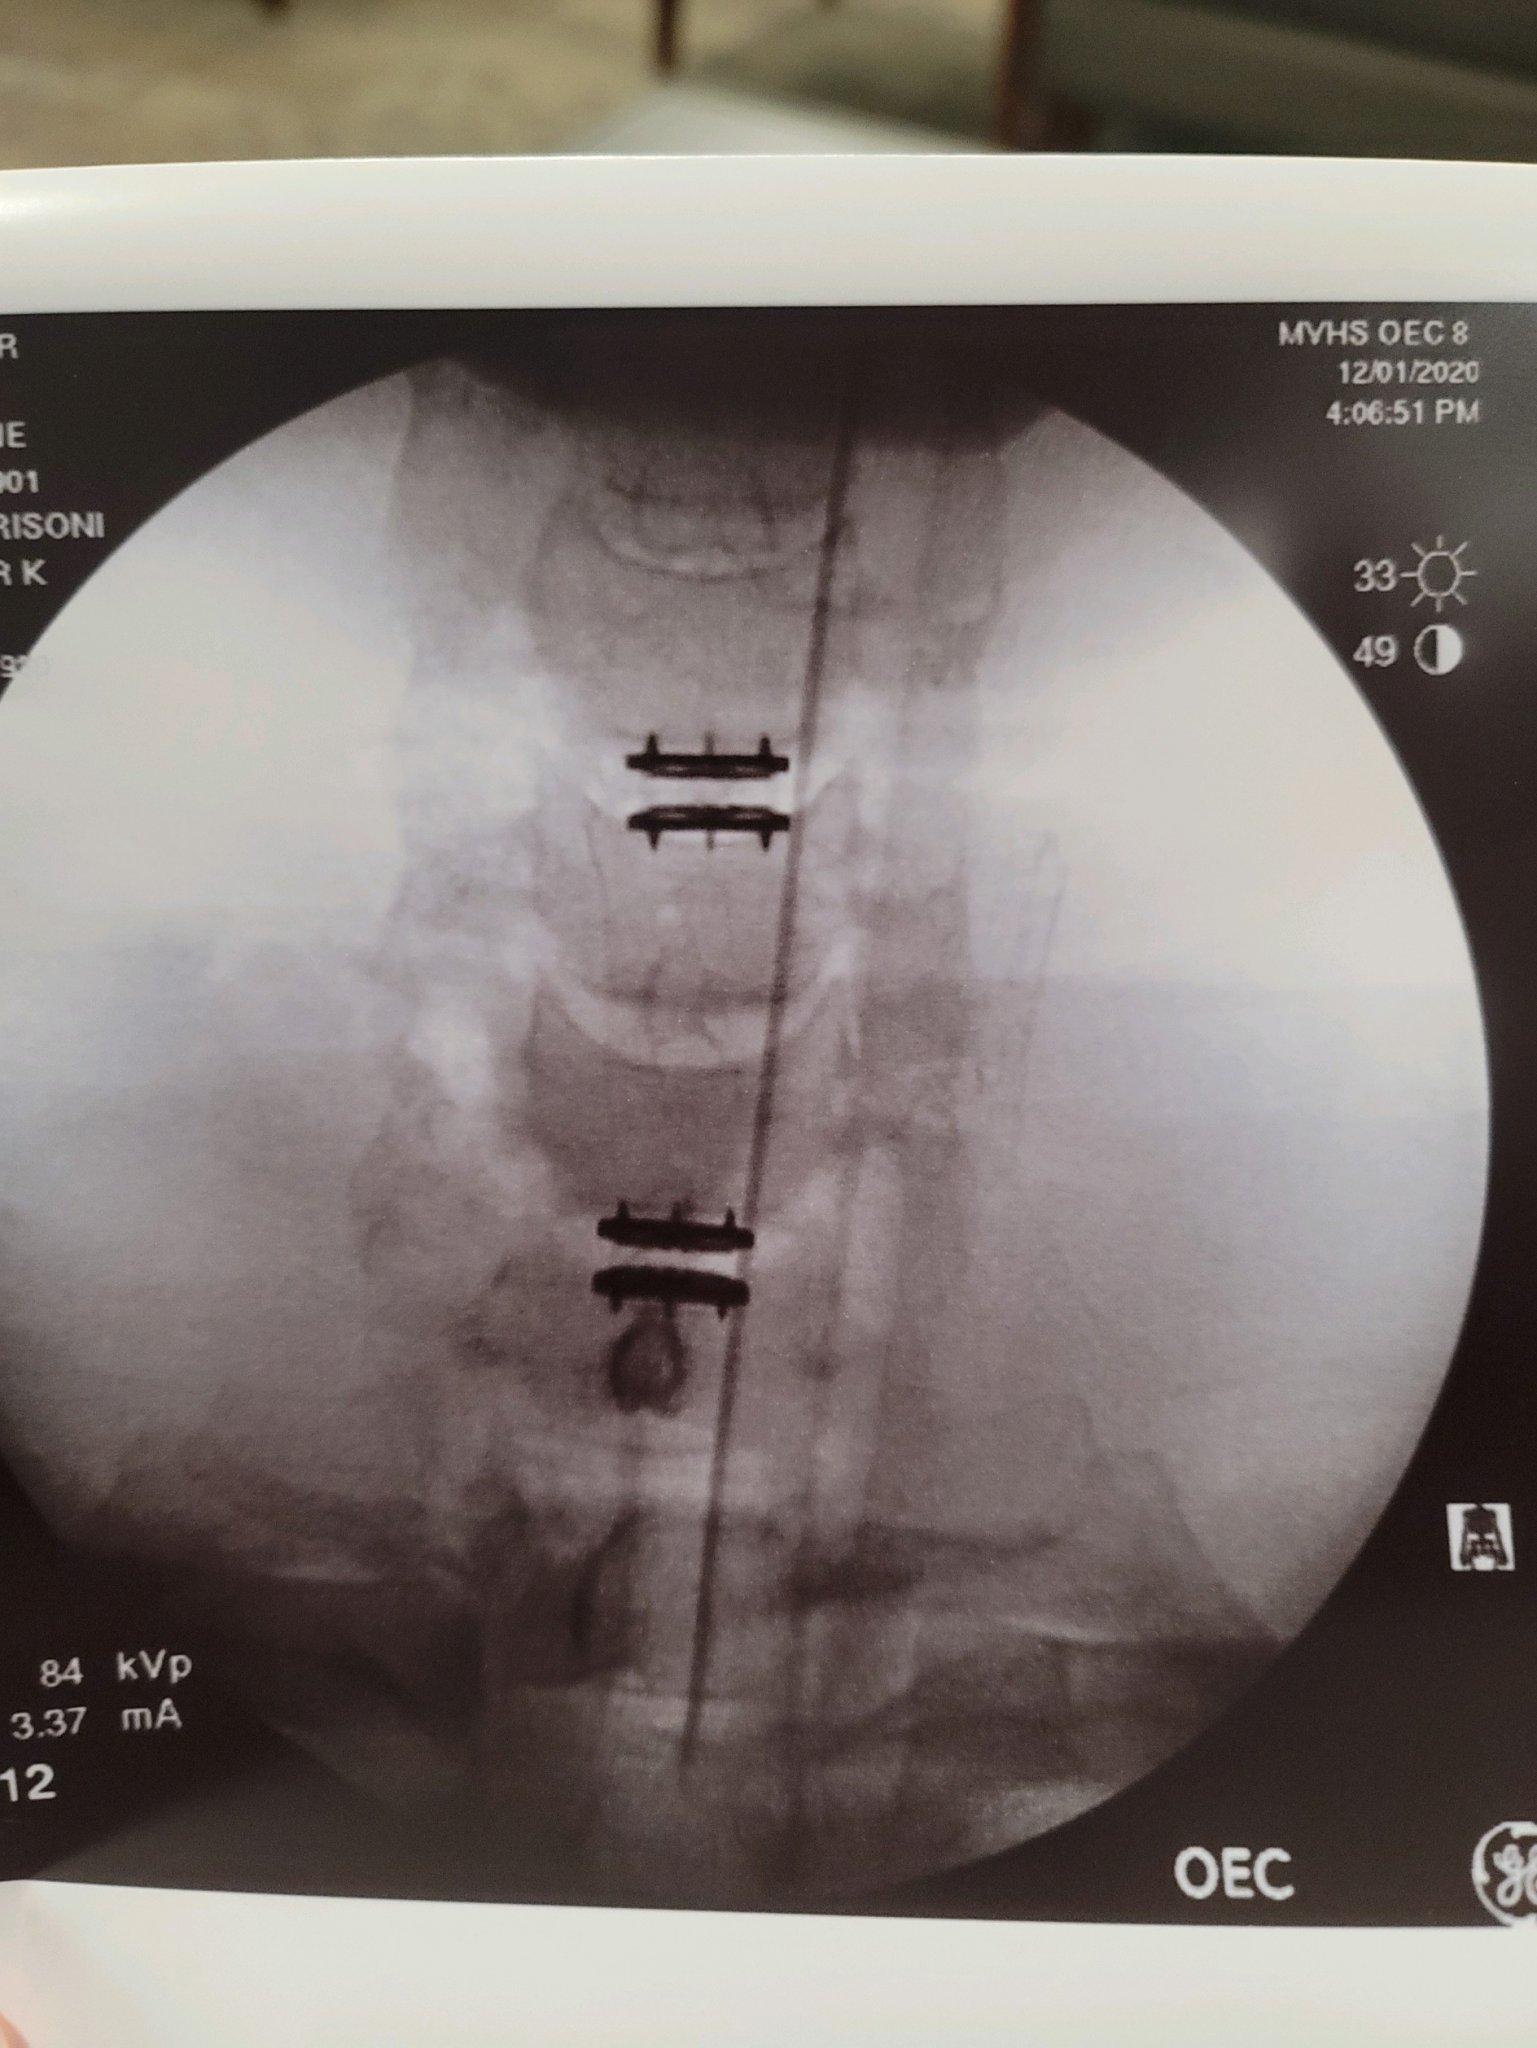

That out of the way I think it was my best decision to have the surgery. I had C3-T1 replaced and fused both anterior and posterior. Immediately after I woke up I had zero pain in my arms and shoulders. It was amazing.

Here are some pics. First two are pre surgery and last two are post surgery.

As far as the 2 level replacements vs 3 level fusion, we discussed my options. I work in EMS and drive a ton. Running lights and siren increases the risk of an accident significantly. Replacements allow more range of motion. I will also be back to work much sooner. He agrees that a 3 level fusion puts me at higher risk of deterioration of the adjacent levels. So he will have to go back in later no matter what. With the 2 level replacements, I mostly have to worry about C5-C6. He can do a fusion of that area later. Since I'll already have the replacements in both adjacent levels, I'm less likely to have complications with them. I trust my doc. He was recommended by one of the physicians that started the pediatric ortho dept at Dayton Children's. The same doc that put rods and screws in my son. Pics included.

As far as the 2 level replacements vs 3 level fusion, we discussed my options. I work in EMS and drive a ton. Running lights and siren increases the risk of an accident significantly. Replacements allow more range of motion. I will also be back to work much sooner. He agrees that a 3 level fusion puts me at higher risk of deterioration of the adjacent levels. So he will have to go back in later no matter what. With the 2 level replacements, I mostly have to worry about C5-C6. He can do a fusion of that area later. Since I'll already have the replacements in both adjacent levels, I'm less likely to have complications with them. I trust my doc. He was recommended by one of the physicians that started the pediatric ortho dept at Dayton Children's. The same doc that put rods and screws in my son. Pics included.